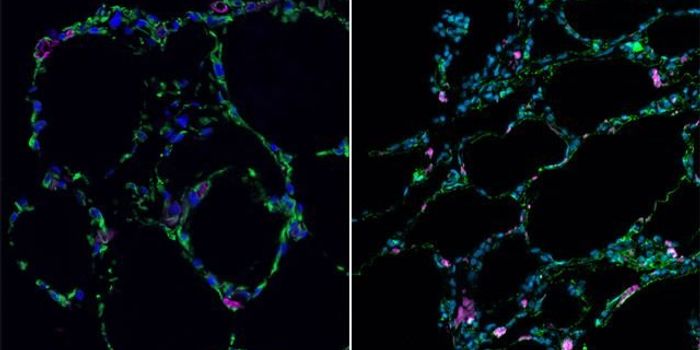

DEC 08, 2013Cell & Molecular BiologyIn a historic first, human stem cells have been coaxed to transforming into living, functioning lung and airway cells. A ...